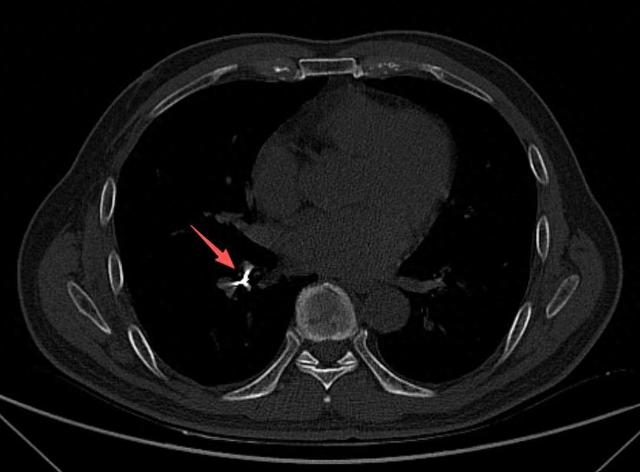

随后,诊所牙医陪同男子到北海市人民医院就诊,经CT检查,在患者右下肺支气管内发现有异物存留,便紧急收入呼吸与危重症医学科病房。

病房接诊后,医院立即启动急诊救治流程。医疗团队为患者取出异物,

经确认,取出的异物正是用于根管治疗的机扩针,长约2厘米,针的一头圆滑、一头细长而尖锐。